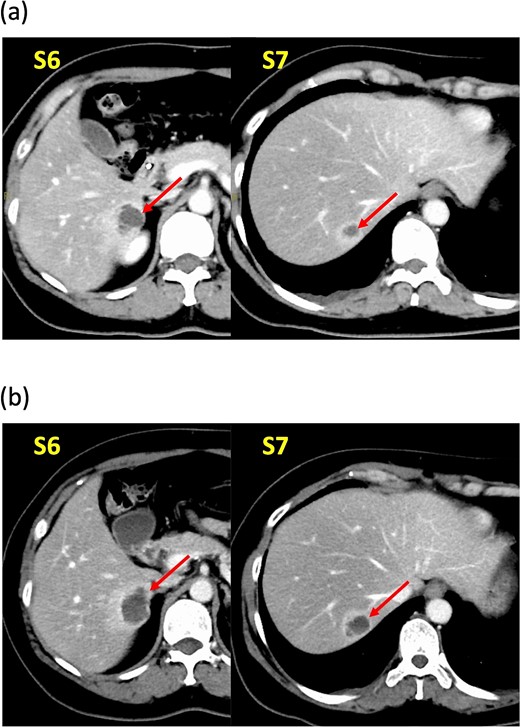

A 52-year-old woman was admitted to our hospital for the evaluation and treatment of multiple cystic liver tumors. Two years earlier, dynamic computed tomography (CT) had detected multiple cystic tumors in segments 6 (S6) and 7 (S7), which were subsequently monitored (Fig. 1a). The patient showed no symptoms; laboratory tests for tumor markers such as α-fetoprotein, protein induced by vitamin K absence or antagonist-II, carcinoembryonic antigen, and carbohydrate antigen 19–9 were within normal ranges. Dynamic CT identified two low-density tumors with peripheral enhancement in the portal phase, featuring cyst-like internal septa (Fig. 1b), which showed slow enlargement over 2 years. Magnetic resonance imaging (MRI) using gadoxetic acid (gadolinium-ethoxybenzyl-diethylenetriamine pentaacetic acid; EOB Primovist®) revealed that tumors appeared as low intensity signals on T1-weighted imaging and high intensity signals on T2-weighted imaging and diffusion-weighted imaging. Additionally, a 7-mm lesion was observed at the S7/8 boundary (Fig. 2a and b). Positron emission tomography-CT (PET-CT) showed abnormal uptake in S6 and S7 tumors but not in the S7/8 lesion (Fig. 3). CT during hepatic arteriography (CTHA) demonstrated well-contrasted tumors at the periphery, with no contrast enhancement in the center (Fig. 4a). Moreover, CTHA detected a new tumor in S8, displaying clear and uniform contrast but not visible with other imaging modalities (Fig. 4b).

Dynamic computed tomography (CT) findings. (a) Two years ago, cystic tumors were detected as low-density lesions surrounded by contrasting tissue in segments 6 (S6) and 7 (S7). (b) Preoperative CT shows both tumors had enlarged slightly.